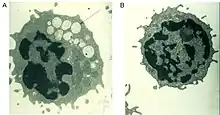

A defective alpha-mannosidase enzyme, which normally helps to break down complex sugars derived from glycoproteins in the lysosome, causes progressive lysosomal accumulation of mannose-rich oligosaccharides in all tissues, resulting in impaired cellular function and apoptosis (Figure 2).[2][8] Complete absence of functionality in this enzyme leads to death during early childhood due to deterioration of the central nervous system.[8] Enzymes with low residual activity lead to a milder form of the disease, with symptoms such as impaired hearing, cognitive impairment, susceptibility to bacterial infections, and skeletal deformities. The course of the disease is progressive.[2][8]